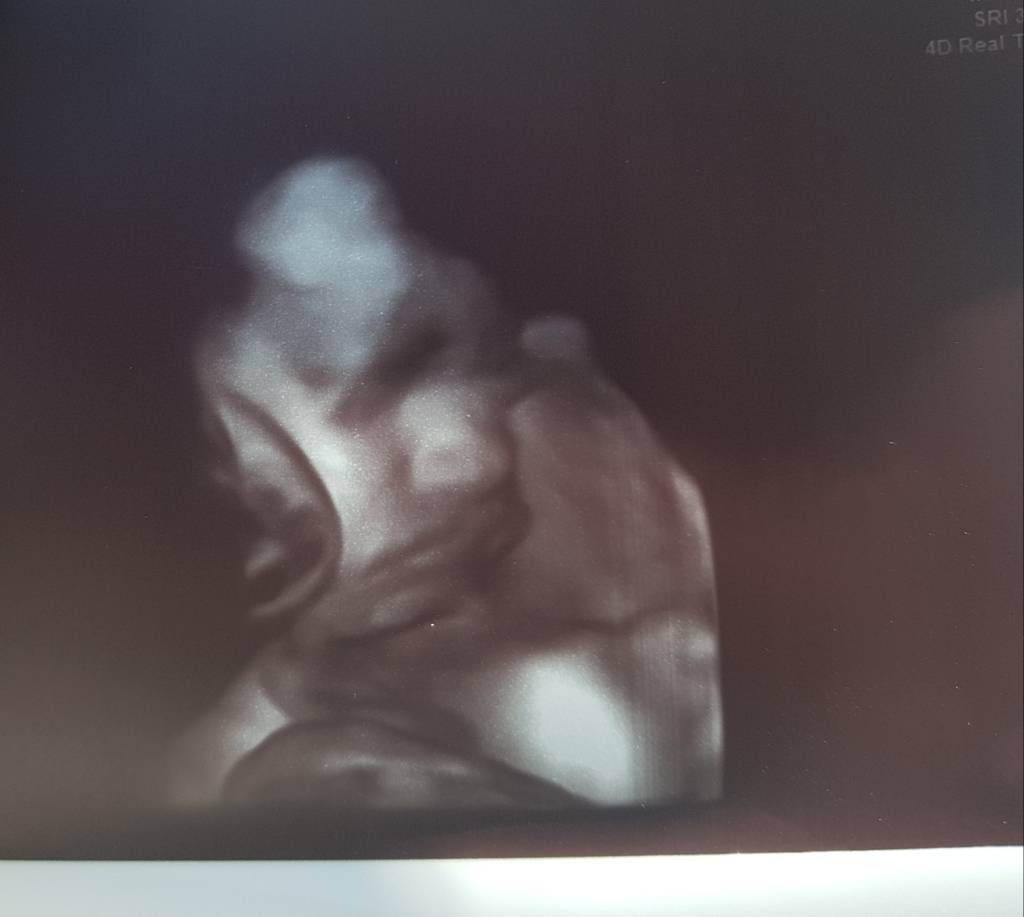

Zobaczcie i internetowe ciotki jaki mój syn naburmuszony jest [emoji16]pewnie mu się nudzi w tym brzuchu [emoji14]

20180823_195253.jpg